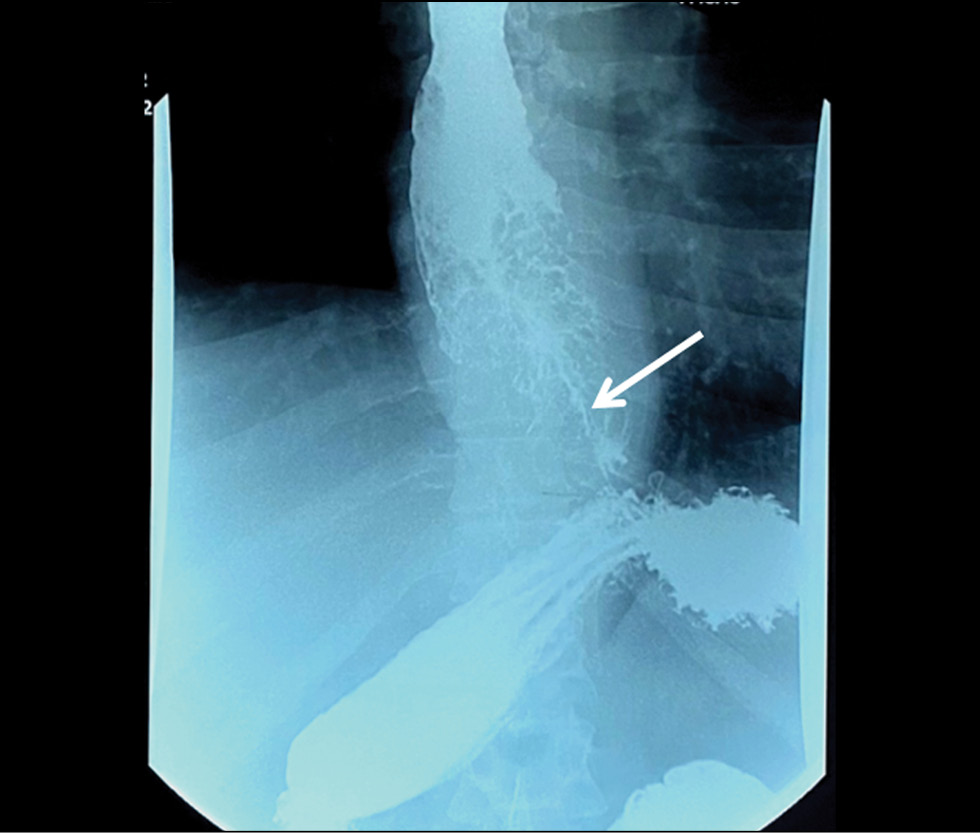

Tissue sampling and histopathological limitations in esophageal cancer

Abstract

Esophageal adenocarcinoma is a common gastrointestinal cancer. Esophagogastroduodenoscopy with biopsy and immunohistochemistry are used to detect the neoplasm at an early stage. Definitive diagnosis requires not only highly specialized equipment but also the skills of the endoscopist and pathologist. We report the case of a 35-year-old man with progressive dysphagia caused by gastroesophageal cancer. Numerous esophagogastroduodenoscopy studies, computed tomography, and barium X-ray swallow revealed an extensive esophageal lesion; however, pathomorphologic examinations did not confirm malignancy within a year. Histological studies showed pyloric gland adenoma and adenoma from parietal or oncocytic cells with high-grade dysplasia. Esophagogastroduodenoscopy with targeted biopsy at a specialized center confirmed the tumor malignancy. This clinical case demonstrates the importance of summing clinical symptoms and using additional instrumental methods to make a definitive diagnosis if biopsy results are ambiguous.

633-642